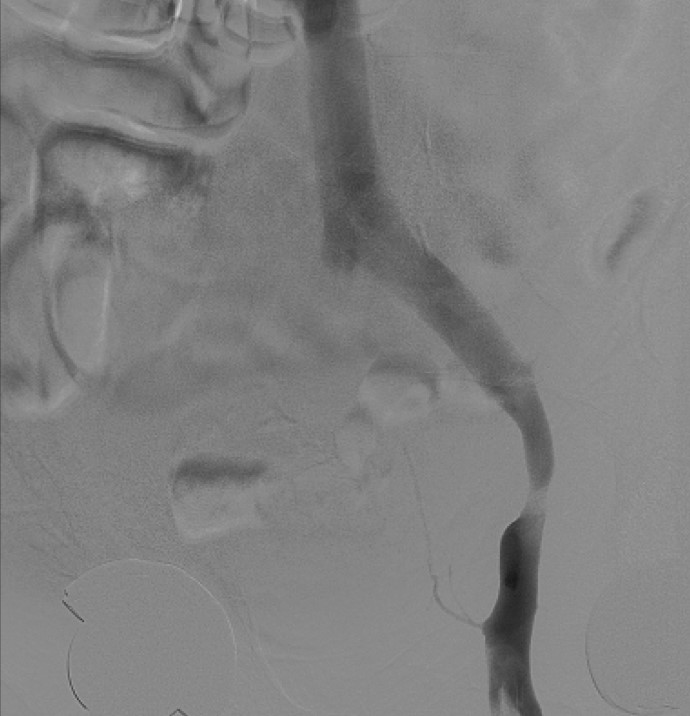

Case Presentation: A 59-year-old male patient with no significant past medical history presented to our hospital with left foot swelling that started almost four weeks prior to presentation. The swelling was progressive, ascending, and associated with erythema. The patient was initially evaluated by his primary care physician who requested a venous Doppler of his lower extremity. This was negative for deep venous thrombosis (DVT), and he was subsequently started on a course of antibiotics due to concern for cellulitis. Despite antibiotic therapy, the patient’s swelling progressed to involve the entire left lower extremity. The patient was started then on conservative venous insufficiency treatment including compression stockings, leg elevation, and later Lasix. Given the patient’s persistent symptoms and lack of improvement despite those measure, he was referred for a venogram which showed patent venous system in the right side but revealed a narrowing in his left external iliac vein, the area of stenosis occurred at the crossing of what looked like a pulsatile artery, at the level of the crossing of the hypogastric artery into the pelvis. The patient underwent angioplasty and stenting of the narrowed vein which he tolerated well. He was later discharged on aspirin, clopidogrel, and a short course of antibiotics, and his swelling resolved completely three weeks later.

Conclusions: This case has two educational objectives, the first of which is the presentation of a rare variant of May-Thurner syndrome which caused unilateral lower extremity swelling in an otherwise healthy middle-age man. This syndrome is usually caused by compression of the left common iliac vein by the overlying right common iliac artery, but in this case, it was caused by the hypogastric artery which is extremly rare. Second, this case demonstrates the importance of keeping a wide differential diagnosis, and to look for the underlying etiology especially in cases of a unilateral lower extremity swelling. The discovery of his anatomical pathology led to the appropriate management of his symptoms, which would have otherwise persisted in the setting of conservative management.